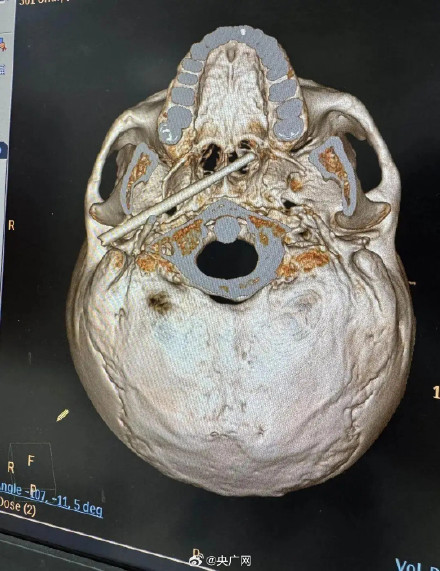

1月10日,来自东莞45岁的陈先生意外被筷子刺入颅底,情况十分危急。据了解,一根筷子意外从陈先生外耳道上方刺入,强大的冲击力不仅穿透了耳部骨质,还一路贯穿侧颅底—咽旁间隙,最终直抵鼻咽部。更令人揪心的是,断裂残留的筷子尖端,距离为大脑供血的主干线——颈内动脉仅5毫米。历经2小时手术,医疗团队成功在“颅底拆弹”,将筷子完整取出,目前患者已转入普通病房。(羊城晚报)